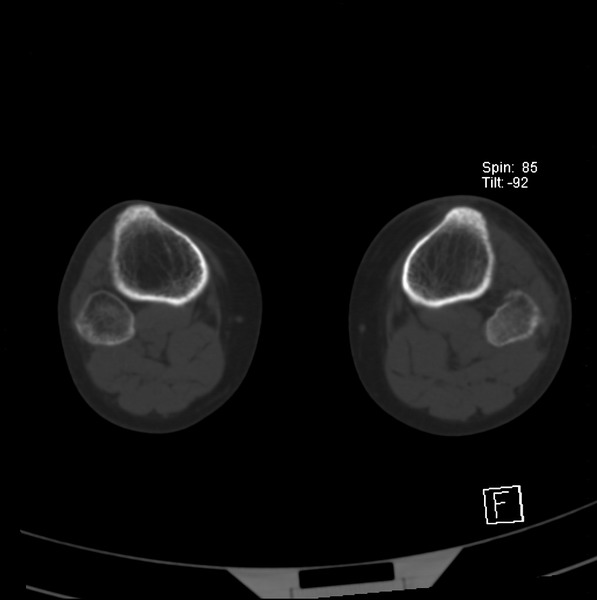

标题: CT21917:右腓骨小头是否骨软骨瘤? [打印本页]

标题: CT21917:右腓骨小头是否骨软骨瘤?

女、43.

不是骨软骨瘤,“牵拽征”,正常变异。有平片吗?

正常变异,“牵拽征”,比目鱼肌牵拽.

比目鱼肌附着点